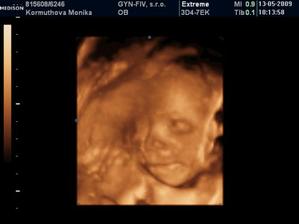

Naše 3D